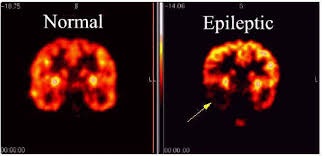

(Epilepsy) ေရာဂါကို ၿမန္မာလို ၀က္ရူးၿပန္ေရာဂါလို႕ အသိမ်ားၾကပါတယ္။ ဒီေရာဂါဟာ ေယာက္်ား မိန္းမ မေရြး အသက္အရြယ္ ကန္႕သတ္ခ်က္မရွိဘဲ ၿဖစ္ႏိုင္ပါတယ္။ ဦးေႏွာက္တြင္းရွိ နာဗ္ဆဲလ္မ်ား ရုတ္တရက္ အလ်င္အၿမန္ လႈပ္ရွားၿခင္းလို႕ အဓိပၸာယ္ဖြင္႕ဆိုထားပါတယ္။ အၿဖစ္အမ်ားဆံုးအသက္အရြယ္ ကေတာ႕ အသက္ ၂ ႏွစ္ေအာက္နဲ႕ ၆၅ႏွစ္အထက္ လူၾကီးမ်ားၿဖစ္ၾကၿပီး ယေန႕ေခတ္မွာေတာ့ သက္လတ္ပိုင္းသူေတြမွာလဲ ဒီေရာဂါအၿဖစ္ မ်ား ပါတယ္။

SUDEP ၿဖစ္ဖို႕ ေၾကာင္းရင္းေတြအမ်ားၾကီးထဲကမွ ေသဆံုးမႈ႕ကိုအမ်ားဆံုးၿဖစ္ေစတဲ႕အေၾကာင္းရင္းတစ္ခုကေတာ႕ ႏွလံုးမွာရွိတဲ႕ လွ်ပ္စစ္လႈံ႕ေဆာ္မႈ႕အား မမွန္ကန္လို႕ၿဖစ္ပါတယ္။

လူတဦး တက္ေနၿပီဆိုတာနဲ႕ ဦးေႏွာက္မွာ ဆဲလ္ေတြ ကစဥ္႕ကလ်ားလုပ္ရွား ရုန္းကန္ၾကပါတယ္ ။ တစ္ခ်ိန္တည္းမွာပဲ ႏွလံုးမွာရွိတဲ႔ ဆဲလ္ ေတြ အဆက္မၿပတ္လႈပ္ရွားလာပါတယ္။အေၿခအေနႏွစ္မ်ိဳးဟာတစ္ခ်ိန္တည္းမွာ အလြန္လွ်င္ၿမန္စြာၿဖစ္ ေပၚပါတယ္။ ေသဆံုးရၿခင္းဟာ ႏွလံုးမေကာင္းလို႔ လို႔ တစ္ထစ္ခ် ေၿပာၿပလို႔မရပါဘူး။ တစ္ခ်ိဳ႕လဲ ႏွလံုးမေကာင္းေပမဲ႔ ဘ၀မွာ အသက္ရွည္စြာေနထိုင္ သြားၾကတာလဲ ေတြ႔ႏိုင္ပါတယ္။

ႏွလံုးေရာဂါႏွင္႕သက္ဆိုင္ေသာဓာတ္ခြဲခန္း ေလ႕လာခ်က္တစ္ရပ္က အထက္ပါႏွလံုးေရာဂါ သည္မ်ားဟာ အတက္ေရာဂါ ၿဖစ္တတ္ၾကတယ္လို႕ေတြ႕ရွိထားပါတယ္။

ဒီလိုရွာေဖြေတြ႕ရွိတာဟာ SUDEP ေရာဂါနဲ႕ေသႏိိုင္မဲ႕သူတဦးဦးကိုေတာ႕ ေသဆံုးၿခင္းကေန ကာကြယ္ႏိုင္ပါလိမ္႕မယ္။

ယခုအခ်ိန္ထိ အတက္ေရာဂါရွိသူမ်ားဟာ ECG လို႕ေခၚတဲ႕ ႏွလံုးစမ္းသပ္မႈ႕ကို ပံုမွန္မစစ္ေဆးတတ္ၾကပါဘူး။ ဒါကလည္း ႏွလံုးေရာဂါနဲ႕ အတက္ေရာဂါ ဆက္စပ္မႈ႕ ရွိ၊မရွိ တိက်ေသခ်ာတဲ႕သက္ေသ ၿပခ်က္ မရွိေသးလို႕ပါပဲ။ ဒါေပမဲ႕ သတိထားၿပီး ႏွလံုးေရာဂါရွိ၊မရွိ စမ္းသပ္လိုက္ပါ၊ ေရာဂါေတြ႕ၿပီဆိုရင္ေတာ႕ ႏွလံုးအထူးကုနဲ႕ အၿမန္ကုသမႈ႕ခံယူပါ။

ဆရာ၀န္မ်ား ကလည္း အတက္ ေရာဂါရွိ တဲ႕လူနာမ်ားကို EEG လို႕ေခၚတဲ႕ ဦးေႏွာက္ဆဲလ္တိုင္းတာမႈ႕ေတြၿပဳလုပ္သလိုပဲ ECG လဲ ၿပဳလုပ္ဖို႕စဥ္းစားသင္႕ပါတယ္။